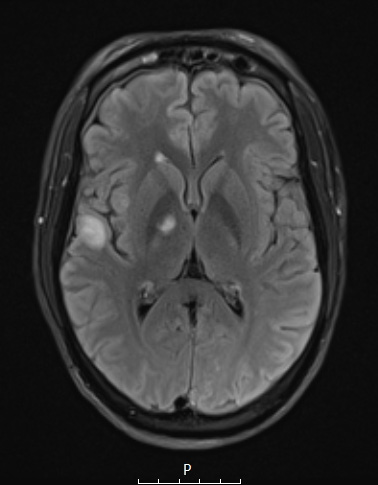

Case 14 History ---- The patient is a 38yo male who presented with bilateral vision loss and multiple brain lesions concerning for demyelinating disease, undergoing resection of a temporal lobe brain lesion. Operative procedure: right temporal lobe craniotomy for resection of the temporal lobe lesion. ---- 14A This FLAIR scan shows severe hyperintense lesions largely in the white matter. The largest lesion was the one biopsied.